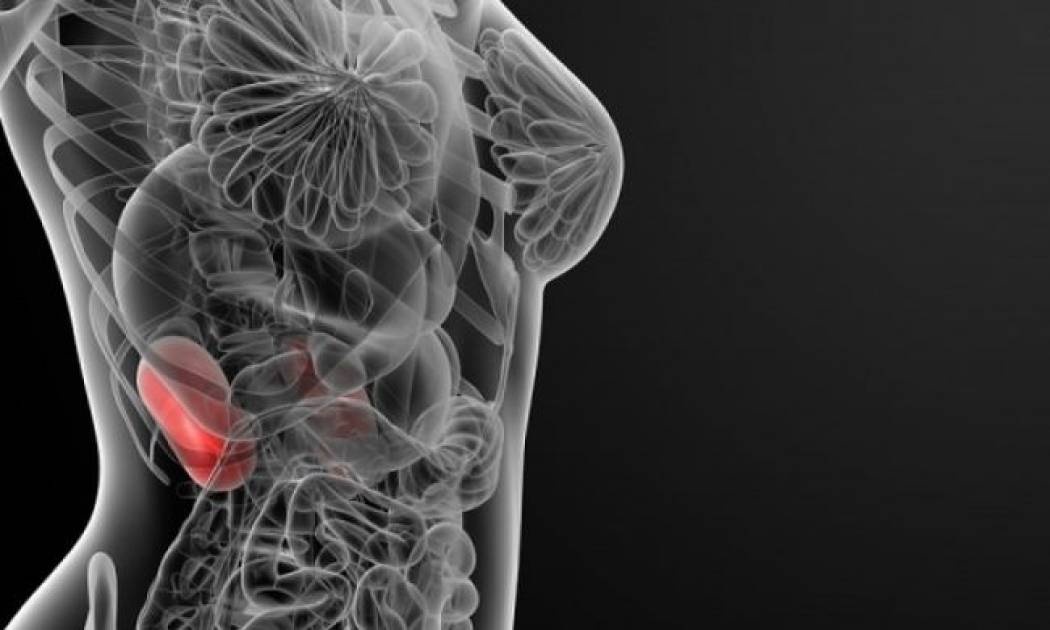

Πέτρες στα νεφρά: Οι 2 θανάσιμοι κίνδυνοι που κρύβουν

Μία νέα έρευνα που δημοσιεύεται στην «Αμερικανική Επιθεώρηση Νεφρικών Νόσων» κρούει τον κώδωνα του κινδύνου για τα άτομα τα οποία πάσχουν από νεφρολιθίαση.

Επιστήμονες από το Ιατρικό Πανεπιστήμιο Guangxi στην Κίνα και άλλα ερευνητικά κέντρα ανέλυσαν συνδυαστικά έξι προγενέστερες επιδημιολογικές μελέτες, στις οποίες είχαν συμμετάσχει 3.558.053 εθελοντές. Επί συνόλου είχαν καταγραφεί 133.589 σοβαρά καρδιαγγειακά επεισόδια, ανάμεσα στα οποία συμπεριλαμβάνονταν εμφράγματα και εγκεφαλικά.